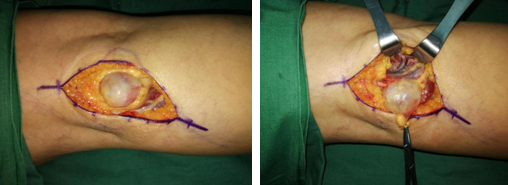

陈步国、吴尧、吴贞志手术团队为王大妈进行了肿物切除手术。术中探查发现一直径约2.8cm的球体肿物,质硬,而神经横穿肿物内侧。手术团队游离肿物外膜,予肿物周围切断神经,完整切除肿物。最后,吻合神经外膜,缝合皮下组织和伤口。

手术很顺利,肿物术后送病理检查,诊断结果示该肿物为神经鞘瘤。

吴医生介绍,王大妈的这个神经鞘瘤没有明确的发病因素。碰触肿物,整个神经支配区域出现放射性麻痛。不管是蹲坐卧,麻痛都很严重,影响生活质量。如果肿物继续增大,卡压胫神经,将会影响足部脚踝的趾屈功能。